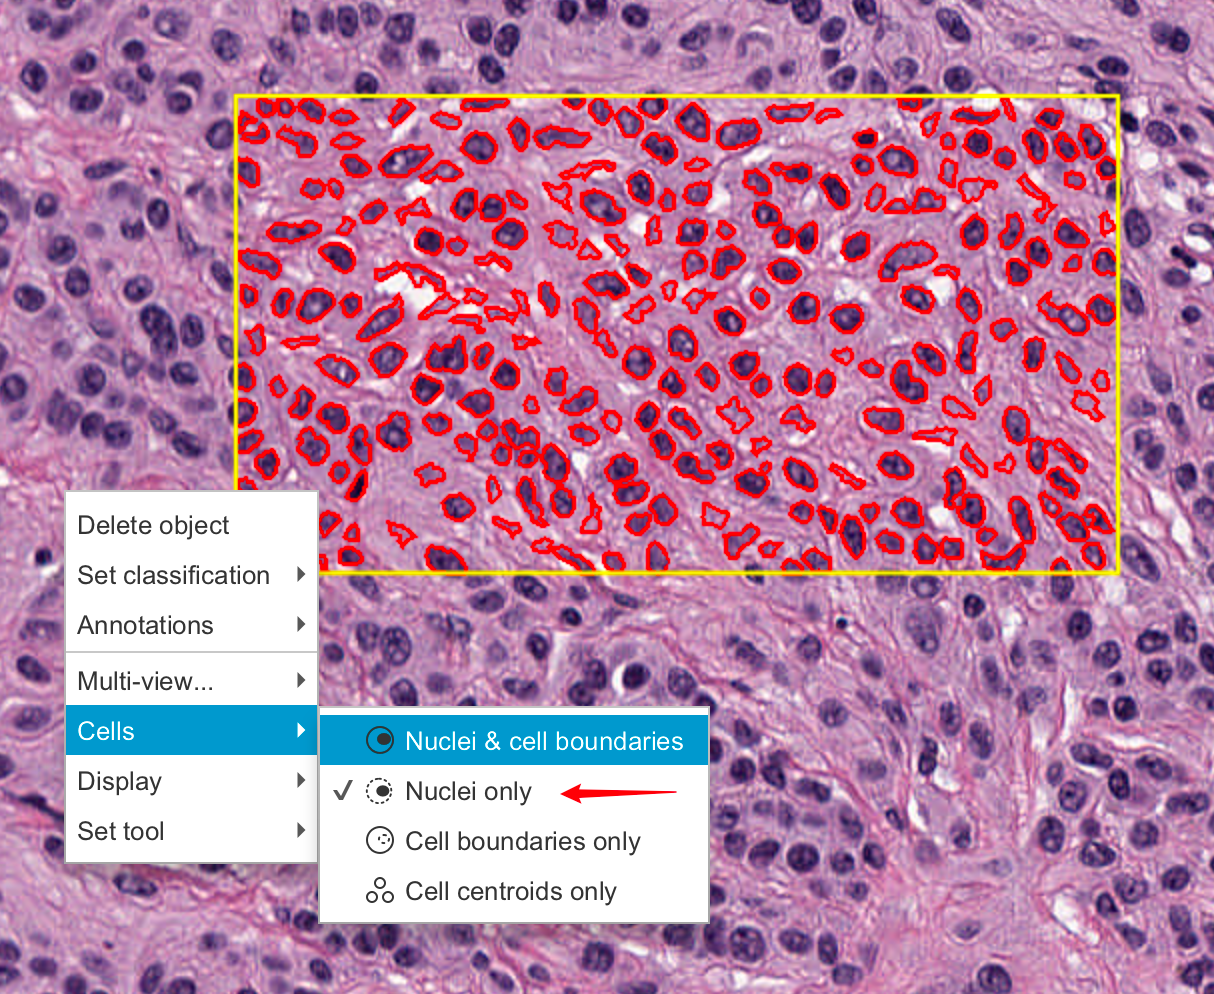

2-9:检测细胞

接下来,尝试在注释内部创建检测对象。首先,在图像中包含细胞的区域绘制一个注释——最好是相当小的区域,包含大约100个细胞。

运行“Analyze ‣ Cell detection ‣ Cell detection”命令。

这应该会显示一个令人望而生畏的参数列表,以适应不同图像的检测。

如果您愿意,可以探索这些参数,并在鼠标悬停在每个参数上以获取描述——但现在,您也可以忽略它们并使用默认值(这些默认值通常在各种图像上表现得相当合理)。

点击对话框底部的“运行”按钮。几秒钟后,您所选区域中的细胞应该会出现。这些细胞是您的第一个检测对象。

2-10:显示与隐藏

随着图像上对象数量的增加,可能会变得杂乱或令人困惑。有四个有用的工具栏按钮可以帮助自定义对象如何显示。

这些按钮允许您快速切换显示标记,以在查看分析数据和底层图像之间切换。

您还可以在图像上右键点击,进一步修改细胞显示的方式,即是否显示核或边界。